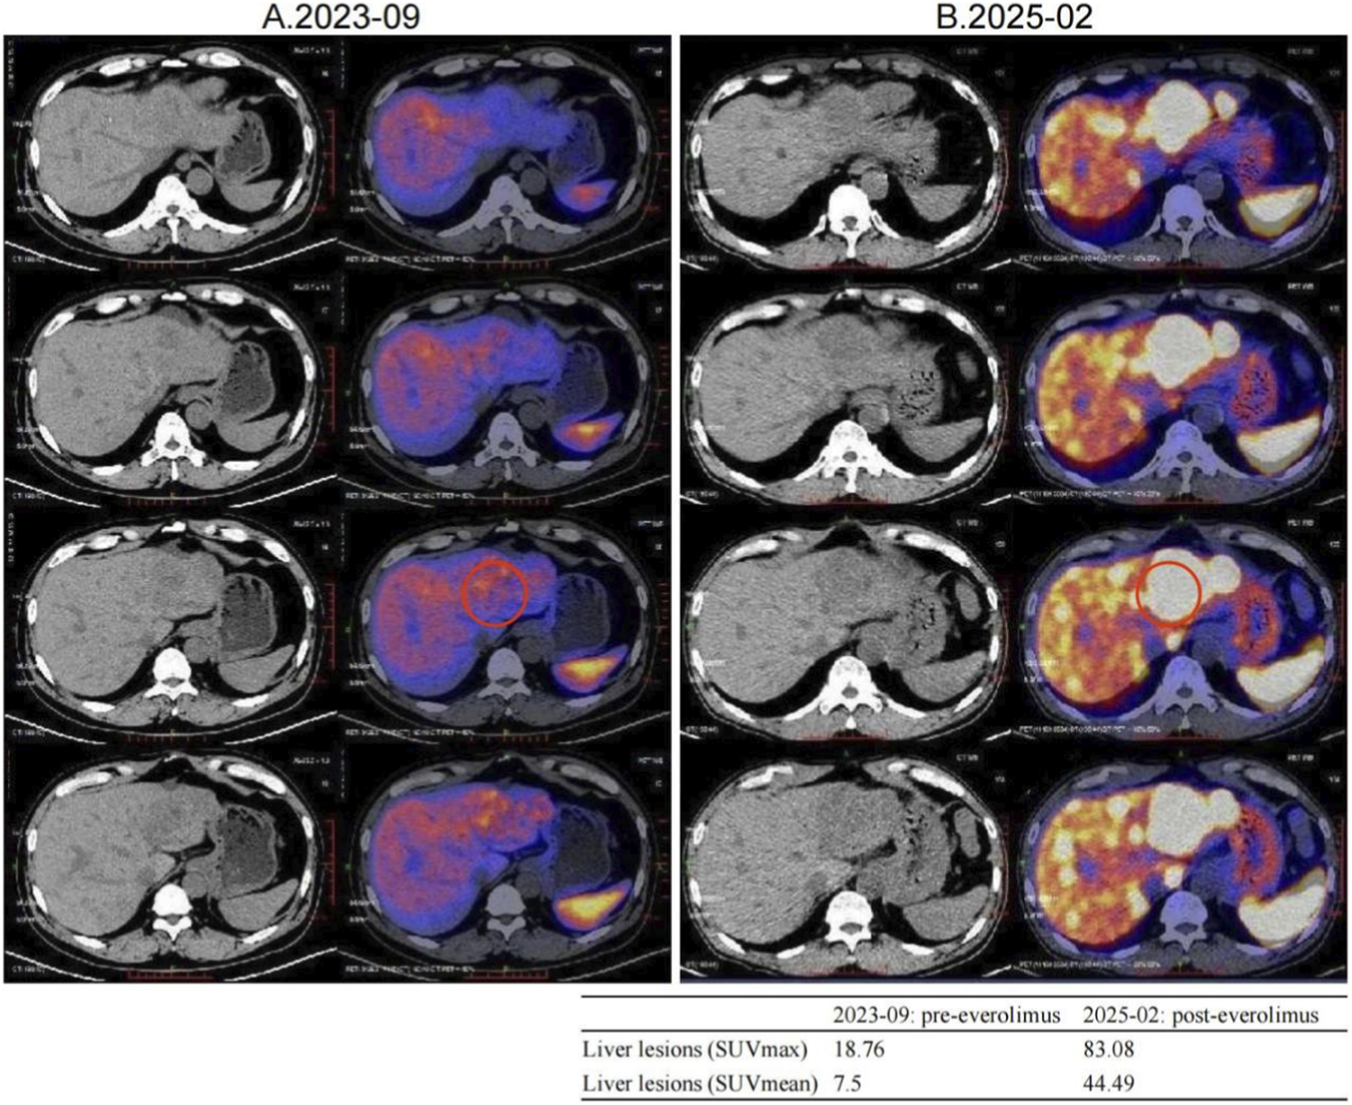

FIGURE 3

Changes in [68Ga]Ga-DOTATATE uptake were noted before and after everolimus, with a representative liver lesion highlighted by a red circle on both PET/CT panels. A small inset table summarizes its SUVmax and SUVmean values pre- and post-treatment. (A) 2023-09 [68Ga]Ga-DOTATATE PET/CT, Intravenous injection of [68Ga]Ga-DOTATATE (4.15 mCi), with whole-body imaging performed at approximately 60 min post-injection. Multiple slightly low-density shadows were seen in the liver parenchyma, and no Ga68 DOTATATE uptake was observed in some lesions within the liver. No increased uptake signals were observed in the abdominal and pelvic cavities. (B) 2025-02 [68Ga]Ga-DOTATATE PET/CT. Intravenous injection of [68Ga]Ga-DOTATATE, 3.13 mCi, followed by whole-body PET/CT imaging at approximately 60 min post-injection. Multiple liver metastases, with a significant increase in Ga68 DOTATATE uptake level compared to 2023-09 PET/CT (SUVmax:83.08). No increased uptake signals were observed in the abdominal and pelvic cavities.

The MDT recommended repeating [68Ga]Ga-DOTATATE imaging to reassess tumor burden and SSTR2 expression. On 12 February 2025, [68Ga]Ga-DOTATATE uptake in multiple hepatic metastases was markedly increased, indicating SSTR2 upregulation following everolimus therapy (Figure 3; Supplementary Tables S1, S2). The patient was then re-screened for the “[177Lu]Lu-DOTATATE Injection versus Long-Acting Octreotide Study” and was randomized to the control arm, receiving 60 mg of long-acting octreotide every 4 weeks, and a CT performed in May 2025 showed SD on response assessment (Supplementary Figures S1, S2).

Notably, this patient exhibited dynamic changes in SSTR expression during everolimus treatment. Pre-treatment [68Ga]Ga-DOTATATE imaging showed negligible uptake, indicating low SSTR expression often seen in poorly differentiated or highly proliferative NETs (Kim et al., 2024). After several months of everolimus, hepatic lesions regained high SSTR expression and “lit up” on imaging—a phenomenon of SSA receptor re-expression that has gained attention (Mileva et al., 2021).

Quantitatively, although SUV_max values of 10–40 are common in well-differentiated NETs, outliers with very high uptake have been reported on [^68Ga]Ga-DOTATATE PET/CT (tumor SUV_max up to 118), so the value of 83.08 observed here falls within published extremes (Kayani et al., 2009). Our two studies were acquired on the same system with ∼60-min uptake times and similar activities, consistent with current SNMMI/EANM procedure standards; thus, protocol differences are unlikely to explain the increase (Hope et al., 2023). The marked rise is more plausibly attributed to high post-treatment SSTR2 availability and favorable background activity (with normal spleen and liver SUVs in the expected ranges), as reflected by elevated tumor-to-liver and tumor-to-spleen ratios now detailed in Supplementary Tables S1, S2.